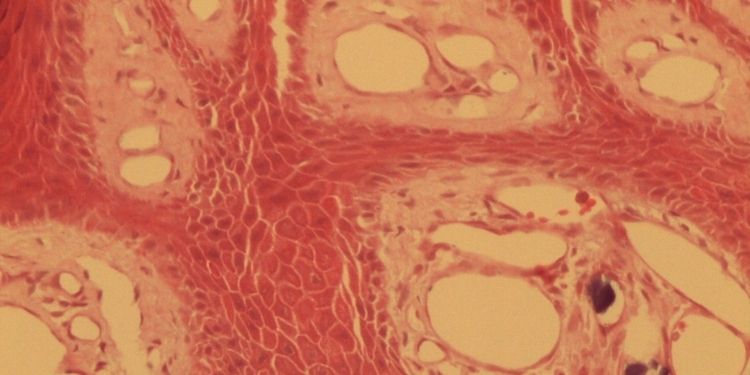

Journal of Etiological Diagnosis-Verruca vulgaris. Calcinosis cutis. Knee.

Calcinosis Cutis on Vulgar Wart. Report of a Case

Published on 31 Mar 2022